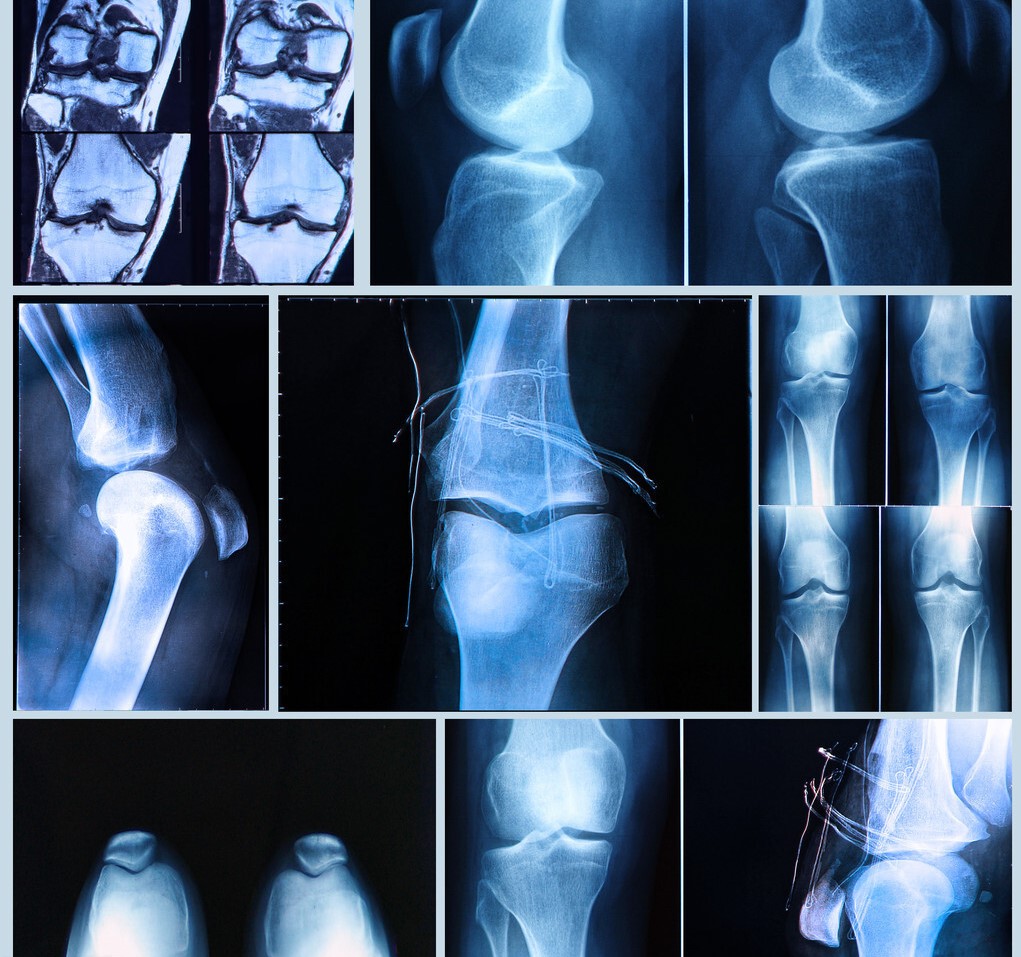

氨基葡萄糖,只对退行性骨关节病有辅助治疗的作用。当人体衰老时,体内合成的氨基葡萄糖数量下降,关节软骨的磨损速度大于修复速度,就会产生疼痛,主要见于承重较大的膝关节。这时适当地补充外源性的氨基葡萄糖,可以提高软骨细胞的修复能力,缓解疼痛,改善关节的功能。

还有部分老年人是腰椎的问题,比如有椎间盘突出或是椎管狭窄,压迫下肢神经,也会造成腿疼的症状。也有人是因为过度锻炼,造成了肌肉、韧带、关节囊、半月板等部位的损伤,引起的疼痛。